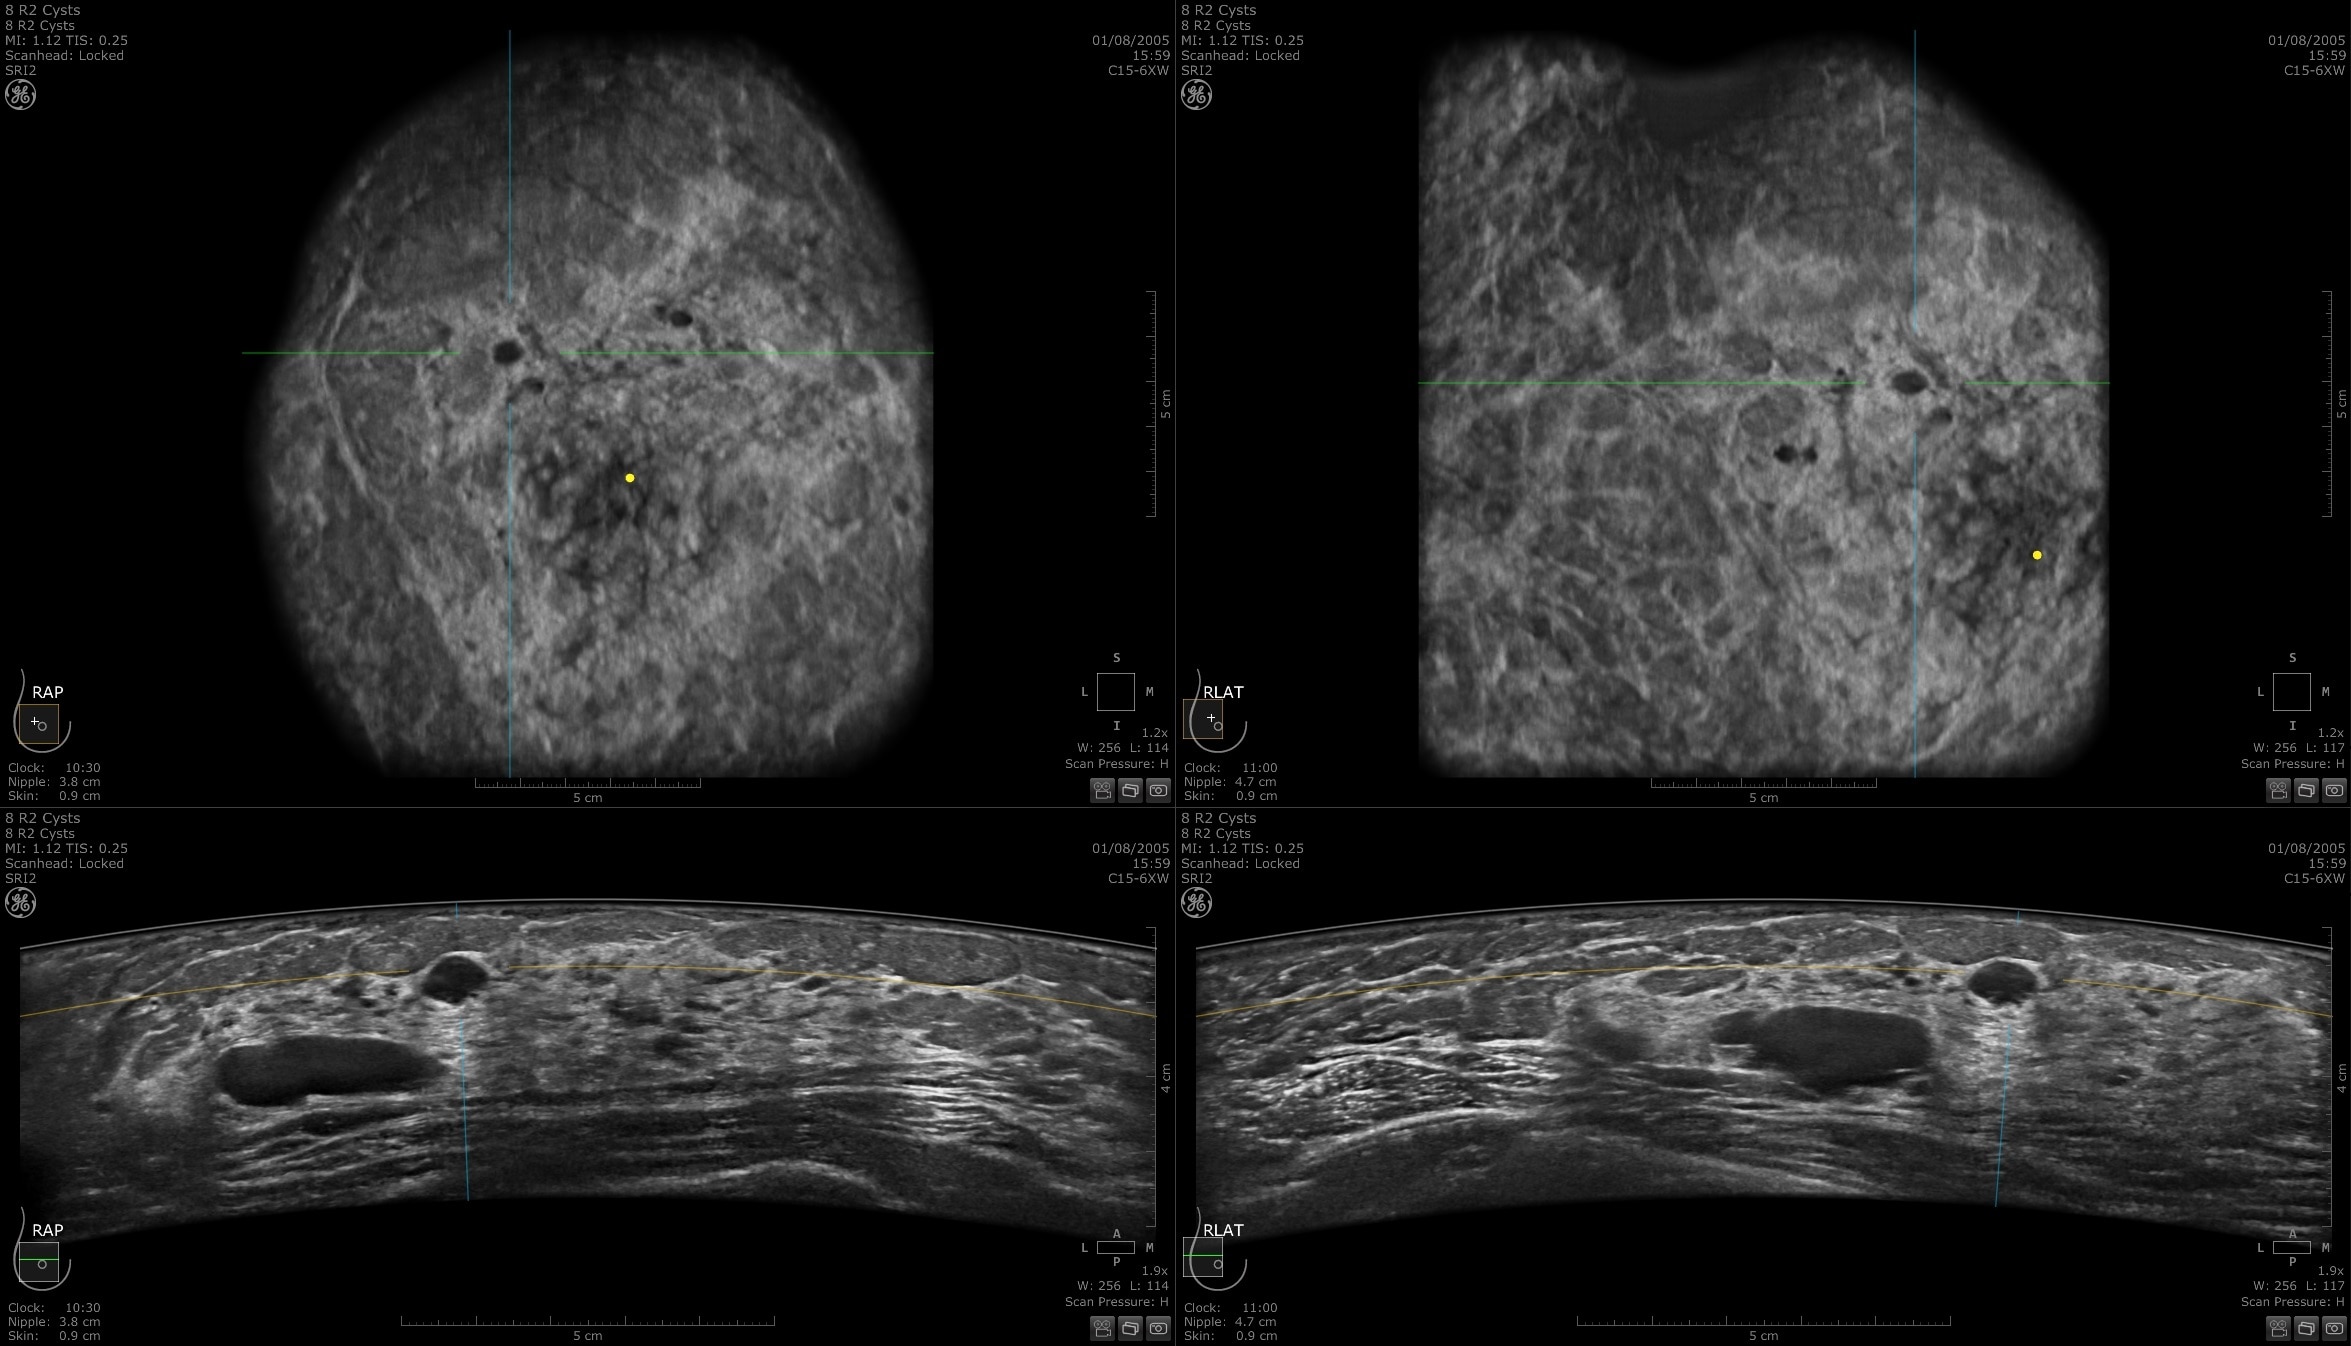

Easy monitoring of treatment progress

Invenia ABUS 2.0 uses patient friendly imaging to help monitor treatment progress with the goal of avoiding complications and risk of cancer recurrence. Features such as auto prior function provide a standardized comparison with previous findings.